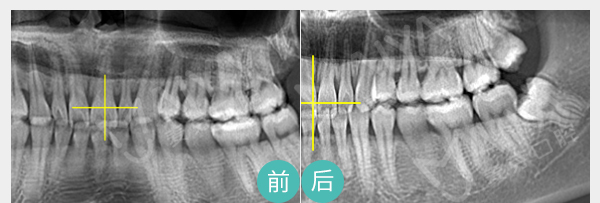

针对牙周炎、不良修复体导致的牙周袋, 麦芽龈下刮治术通过精密器械,清除根面结石和菌斑创口小愈合快,但建议根治牙周炎或更换不良修复体,才能治本

适应症:牙龈炎、牙周炎、 牙周袋、不良修复体引起的口臭